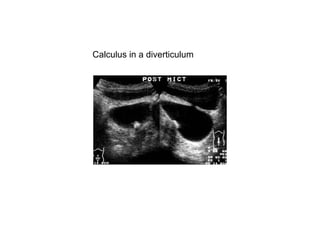

Calculus in a diverticulum